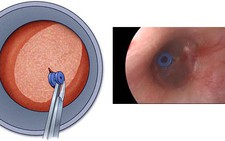

Bệnh tai của những người bơi lội (hay Swimmer’s ear) là tên gọi thông thường của bệnh viêm tai ngoài (otitis externa). Đây là một tình trạng nhiễm trùng điển hình của da ống tai gây ra do sự tiếp xúc với nước thường xuyên hoặc trong thời gian dài. Việc tiếp xúc này đã tạo môi trường ẩm ướt trong ống tai, tạo điều kiện thuận lợi cho các tác nhân gây bệnh như (vi trùng, nấm…) phát triển.

Bất cứ ai cũng có thể bị bệnh lý viêm tai ngoài, tuy nhiên tần suất mắc bệnh cao nhất gặp ở trẻ em. Do đó chúng ta cần phân biệt bệnh lý viêm tai ngoài với bệnh lý viêm tai giữa cũng là một bệnh khá thường gặp, xảy ra sau khi trẻ bị những đợt nhiễm trùng hô hấp trên như cảm thường, viêm mũi, viêm xoang…